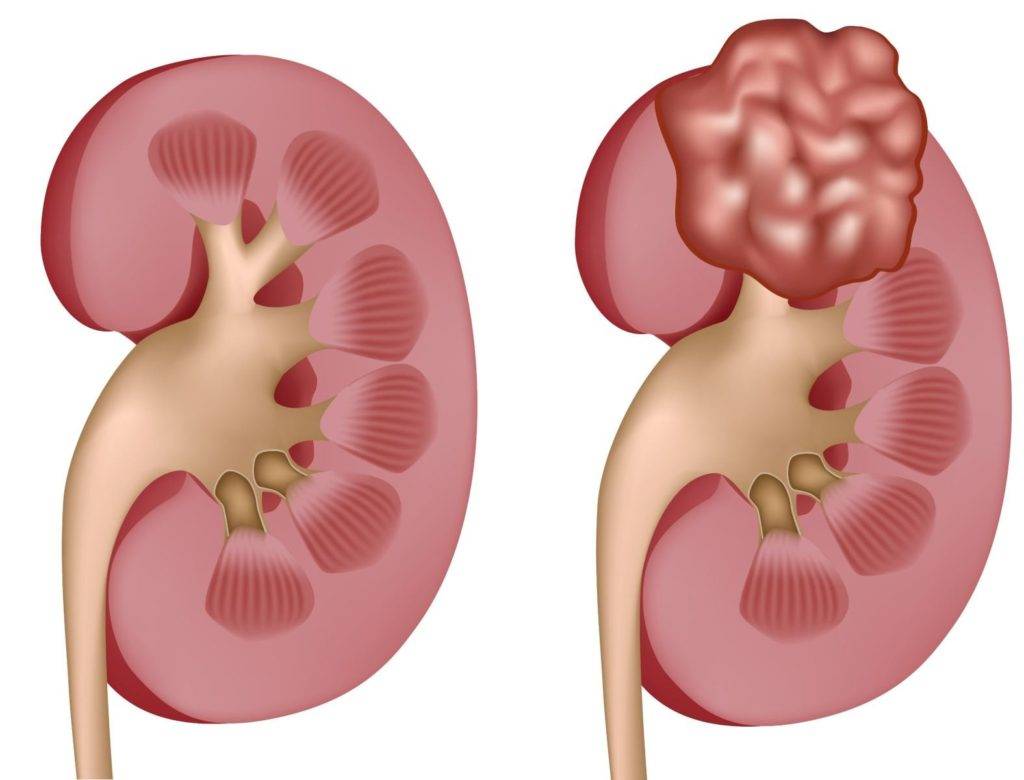

Метастазы в почке

Определить, сколько человеку осталось жить при наличии очагов в почке можно в зависимости от степени развития заболевания. Через почки вторичные опухоли могут переноситься кровью и лимфой, что значительно увеличивает вероятность их появления. Наиболее часто данное патологическое состояние наблюдается, если злокачественное новообразование находится в таких органах, как:

- Глотка;

- Кишечник;

- Гортань;

- Молочная железа и т.д.